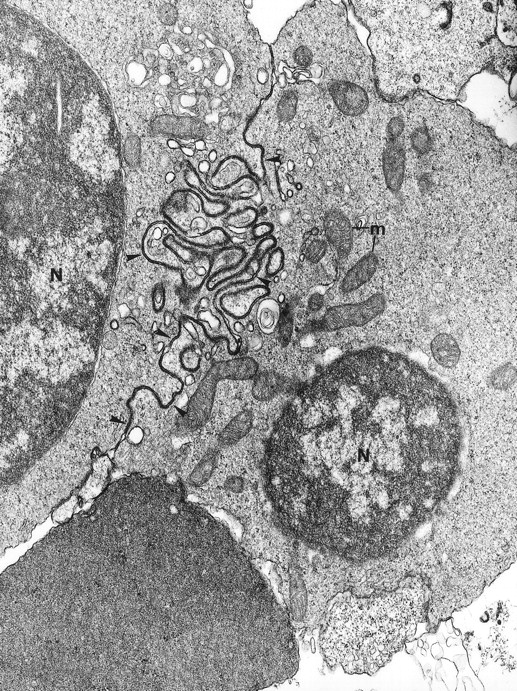

Electron microscopy confirmed the diagnosis of erythroblastic synartesis in the 3 patients. Plasma membranes of adjacent erythroblasts were joined by closely interdigitating processes (Fig2). Cytochemical demonstration of the peroxidatic activity of hemoglobin (not shown) allowed identification of maturation stages of the erythroblasts, because its level of intensity relates to the hemoglobin content of each cell. This technique showed that erythroblasts of the same maturation stage, as well as those of different maturation stages, were linked. Ribosomes were absent at sites of linkage via interdigitating process, corresponding with the nonbasophilic areas observed by light microscopy (Fig3a). At the junction sites, coated pits and rhopheocytosis vesicles were absent, probably because a macrophage expansion would find it impossible to penetrate this zone of tightly linked plasma membrane. Ferritin granules were never observed within these junctions. Junctions between erythroblasts had a characteristic morphology: resembling gap junctions, they were formed by 2 closely placed membranes joined by periodical structures every 150 Å, giving rise to a zipper-like appearance (Fig 3b). Isolated normoblasts often displayed picnotic nuclei and/or binuclearity. The 2 external leaflets of the plasma membrane of adjacent erythroblasts were separated by a constant space of 145 Å in patient 1, and 180 Å in patients 2 and 3.

(a) High magnification of the cell junction between 2 erythroblasts: The electron dense tracer of the extracellular space, tannic acid, decorates the intercellular space. The cytoplasm density of the 2 cells (1 and 2) is unequal, showing that different maturation-stage erythroblasts can be linked together. N, nucleus. Original magnification ×41,400. (b) At a higher magnification, these cell junctions display a septate-like structure (arrowheads). Original magnification ×177,000.

(a) High magnification of the cell junction between 2 erythroblasts: The electron dense tracer of the extracellular space, tannic acid, decorates the intercellular space. The cytoplasm density of the 2 cells (1 and 2) is unequal, showing that different maturation-stage erythroblasts can be linked together. N, nucleus. Original magnification ×41,400. (b) At a higher magnification, these cell junctions display a septate-like structure (arrowheads). Original magnification ×177,000.

Typical synartesis (arrows) can be induced between control erythroblasts, when grown in the presence of patient isolated IgG fraction (shown here, patient 2). Original magnification ×16,100.

Typical synartesis (arrows) can be induced between control erythroblasts, when grown in the presence of patient isolated IgG fraction (shown here, patient 2). Original magnification ×16,100.